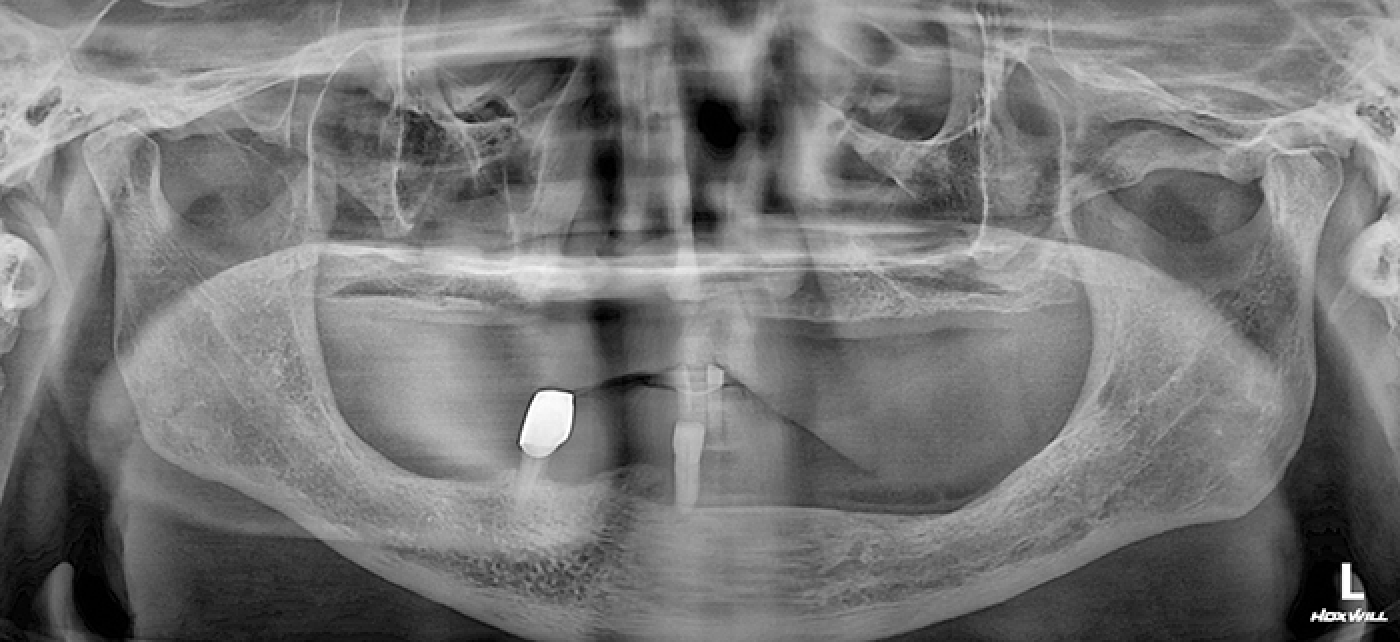

• 임플란트 전

Before

2021년 07월

• 수술 전 x-ray